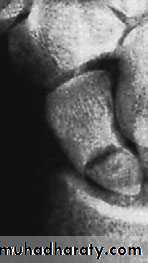

X-ray

Anteroposterior, lateral and oblique views are all essential; often a recent fracture shows only in the oblique view. Usually the fracture line is transverse,and through the narrowest part of the bone (waist), but it may be more proximally situated (proximal pole fracture). Sometimes only the tubercle of the scaphoid is fractured.Treatment